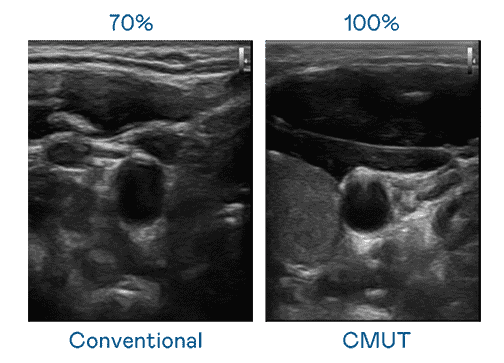

CMUT 技术是一种用电容式微机电元件来产生超音波讯号的技术。。与传统 PZT 压电式技术相比,,CMUT 频宽增加 30%,,更宽频的超音波讯号让影像解析度大幅提升,,是实现高影像品质医疗超音波扫描、、促进精准医疗发展的关键技术。。。

大频宽带来超清晰影像

超音波影像的解析度高低,,,首先取决于探头能发出的讯号频宽。。。。杏悦2 CMUT 可提供高清晰的超音波讯号,,,提供高频宽、、高灵敏度、、影像纹理细节更高的超音波影像,,,,协助医护人员缩短影像判读时间及利用精准的医疗影像进行诊断。。。